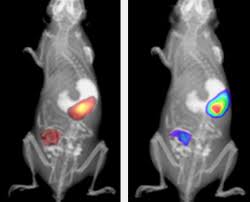

Aparat do przyżyciowego obrazowania zwierząt laboratoryjnych IVIS Lumina XRMS przeznaczony jest do badań dwuwymiarowych z zastosowaniem obrazowania luminescencyjnego, fluorescencyjnego oraz obrazowania promieniowania Cerenkova, a także RTG. Umożliwia to uzyskiwanie złożonych obrazów sygnałów fluorescencyjnych lub /i luminescencyjnych w kontekście obrazu RTG budowy anatomiczne zwierzęcia. Zaawansowana optyka, duży wybór filtrów wzbudzeniowych i emisyjnych, technologia Spectral Unmixing oraz wyposażenie dodatkowe takie jak dedykowany system anestezji gwarantują szerokie spektrum zastosowań aparatów IVIS Lumina XMRS zarówno w badaniach nad nowymi lekami, komórkami macierzystymi, rozwojem stanu zapalnego jak i w badaniach nad terapiami spersonalizowanymi. Standaryzacje badań gwarantuje możliwość absolutnej kalibracji zgodnej ze standardami NIST.

- Technologia Spectral Unmixing

- Moduł obrazowania Rentgenowskiego

Wysoka czułość obrazowania w zakresie luminescencji oraz promieniowanie Cerenkova

Obrazowanie fluorescencyjne do bliskiej podczerwieni

- Możliwość składania obrazów z fluorescencyjnych, luminescencyjnych i RTG.